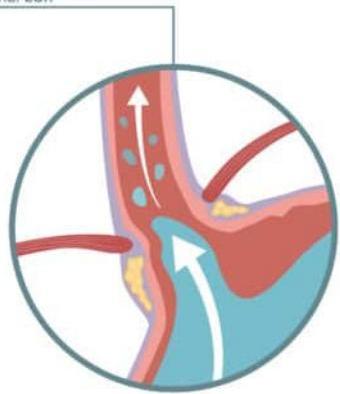

Pathophysiology

Gastroesophageal reflux (GER)

- It is a digestive disorder that affects lower esophagus sphincter (LES). The ring of muscle between esophagus and stomach.

GERD

In pediatric gastroesophageal reflux disease (GERD), immaturity of lower esophageal sphincter function is manifested by frequent transient lower esophageal relaxations, which result in retrograde flow of gastric contents into the esophagus.

Return of the stomach contents back up into esophagus irritate the esophageal mucosa causing esophagitis.